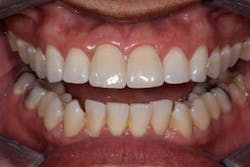

Now comes the tricky part — the provisional. Prosthetic control of peri-implant tissue is achieved by properly utilizing your abutment and provisional form. When placing the provisional, it is important to maintain gingival zenith. When fabricating a provisional, my rule of thumb is to create a flat or slightly convex surface facially and lingually, and a concave surface interproximally. This will minimize impingement on the tissue interproximally and, if anything, allow for “overgrown tissue” to develop. This tissue can be easily contoured prior to final placement to give an ideal esthetic gingival architecture.

Usain Bolt trained for years to prepare for a 10-second Olympic race, a race that made him a world superstar. He didn’t walk up to the track the day of the Olympics and blow away the competition. He spent countless hours preparing physically and mentally for that one moment in the spotlight. The same dedication applies to dentistry. When an anterior implant case is planned properly among the surgeon, dentist, and ceramist, the result can be as rewarding as Olympic gold.Before